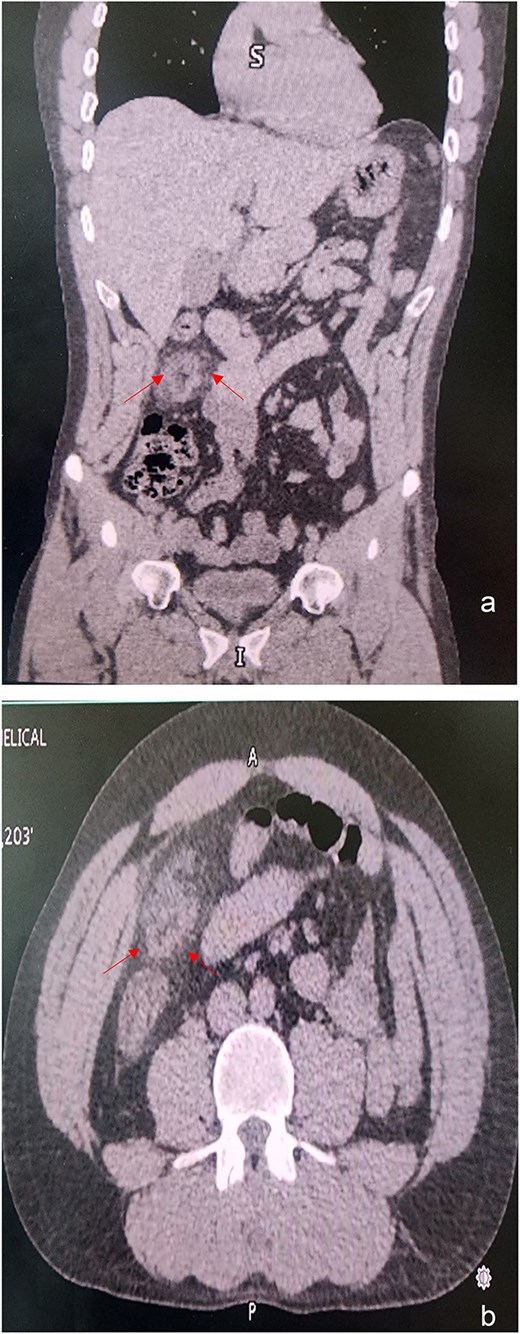

(a) A simple coronal and (b) axial CT showing the density of intra-abdominal fat on the right side was markedly increased, indicating inflammation of the greater omentum.

At the admission, his laboratories were TP 12.3 s, INR 1.07 s, TTP 30 s, leukocytes 10.4 μ/l, neutrophils 76.8 μ/l, hemoglobin 17.6 g/dl, hematocrit 52%, platelets 304 μ/l, fibrinogen 573 mg/dl, glucose 101 mg/dl, bun 11 mg/dl, urea 24 mg/dl, creatinine 1.0 mg/dl, NA 136 mg/dl, K 4.4 mg/dl, CL 98 mg/dl, protein C reactive 1.2 mg/l, procalcitonin 0.036 ng/l. Abdominal CT showed mild thickening of the appendix, which was not enough to diagnose appendicitis definitively. However, it did show that the greater omentum locally hyperdense fat, which was not consistent with peri-appendiceal inflammatory changes seen in appendicitis. The patient was brought to the operating room for a diagnostic laparoscopy (Fig. 1).